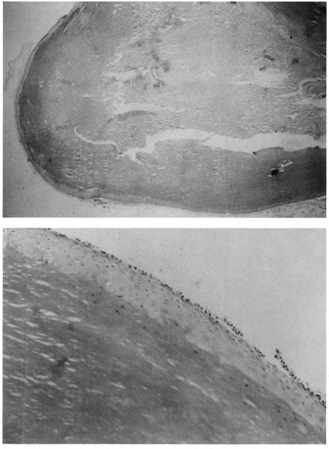

Histologic findings in normal periorbital skin are similar to other areas of the body with a keratinizing epidermis and a prominence of sebaceous glands and blood vessels (Fig. 1, A and B). Lid skin is very thin, its epidermis is composed of only a few layers of keratinocytes (squamous cells), there is an absence of the typical rete ridge (digitated) pattern, and there is a sparse dermis composed of fine fibrillar collagen fibers. Virtually every inflammatory dermatosis and cutaneous neoplasm may, at times, affect the periorbital skin and lids, but some inflammatory processes and neoplasms are commonly seen in this area, and a few are quite specific to the area.

Fig. 1. A. Photomicrograph of normal periorbital skin. B. Schematic of normal periorbital skin.